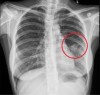

Bệnh lý tim mạch tiếp tục là nguyên nhân hàng đầu gây tử vong toàn cầu. Sự phát triển vượt bậc của các kỹ thuật chẩn đoán hình ảnh không xâm lấn và xâm lấn đã cách mạng hóa quy trình chẩn đoán, phân loại nguy cơ và định hướng điều trị. Bài báo này tổng quan về vai trò lâm sàng, ưu nhược điểm của các phương pháp chủ lực bao gồm Siêu âm tim, Chụp cắt lớp vi tính (CT) mạch vành, Cộng hưởng từ (MRI) tim và Chụp mạch xóa nền (DSA), đồng thời cập nhật xu hướng tích hợp Trí tuệ nhân tạo (AI) trong lĩnh vực này.